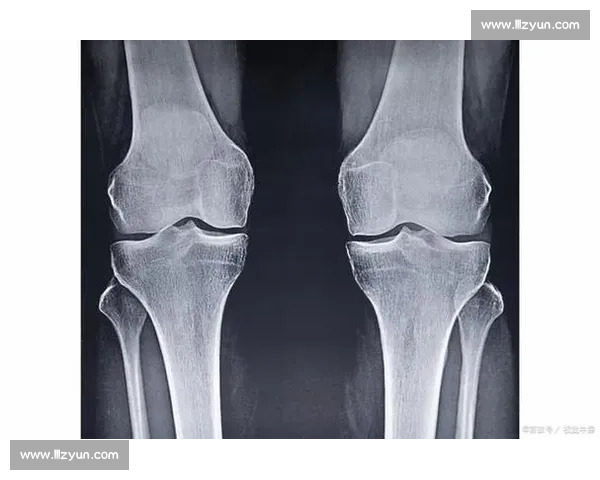

- 骨龄检测:建议先到三甲医院进行左手腕 X 光片检查,通过 Greulich-Pyle 图谱评估骨龄。若骨骺线未闭合,可在医生指导下进行生长激素激发试验。